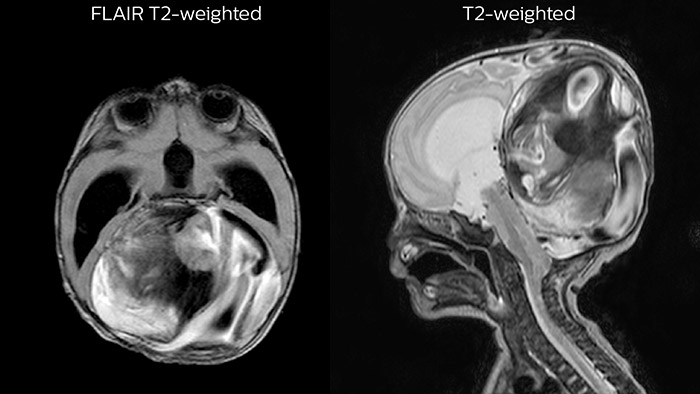

Dural sinus malformation (DSM) Initial examination

After three times of coiling and acryl based embolization

Hydrocephalus post hemorrhagic Both pictures show a ventriculoperitoneal shunt. With our previous scanner our hydrocephalus protocol needed about 25 min. With Ambition the examination time is about 14 min. including a CSF PCA sequence to show flow in the aqueduct.

Rostral meningitis and arachnoiditis Both images are from the same 3D T1-weighted post contrast sequence in a newborn, under treatment.